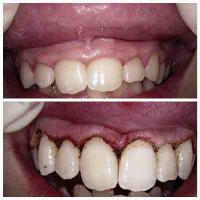

Laser Gum Contouring / Gummy Smile Correction

In the past, patients who were troubled with "gummy" smiles could have the prominence of their gums reduced with a scalpel, which could cause bleeding and an uncomfortable recovery. Now, with the advent of laser dentistry technology, and tools such as the diode laser, patients can have their gums sculpted to perfectly accent their smiles in a fast, simple, and virtually painless procedure.

To begin the laser gum recontouring process, your mouth is numbed with a local anesthetic to eliminate any discomfort. We will then use a diode laser to gently cut away excess gum tissue and sculpt a more uniform, scalloped gum line. Diode lasers cauterize while they cut, which means less bleeding and a dramatically reduced chance of infection for patients. The entire gum lifting procedure can be completed in just one brief visit to our office.